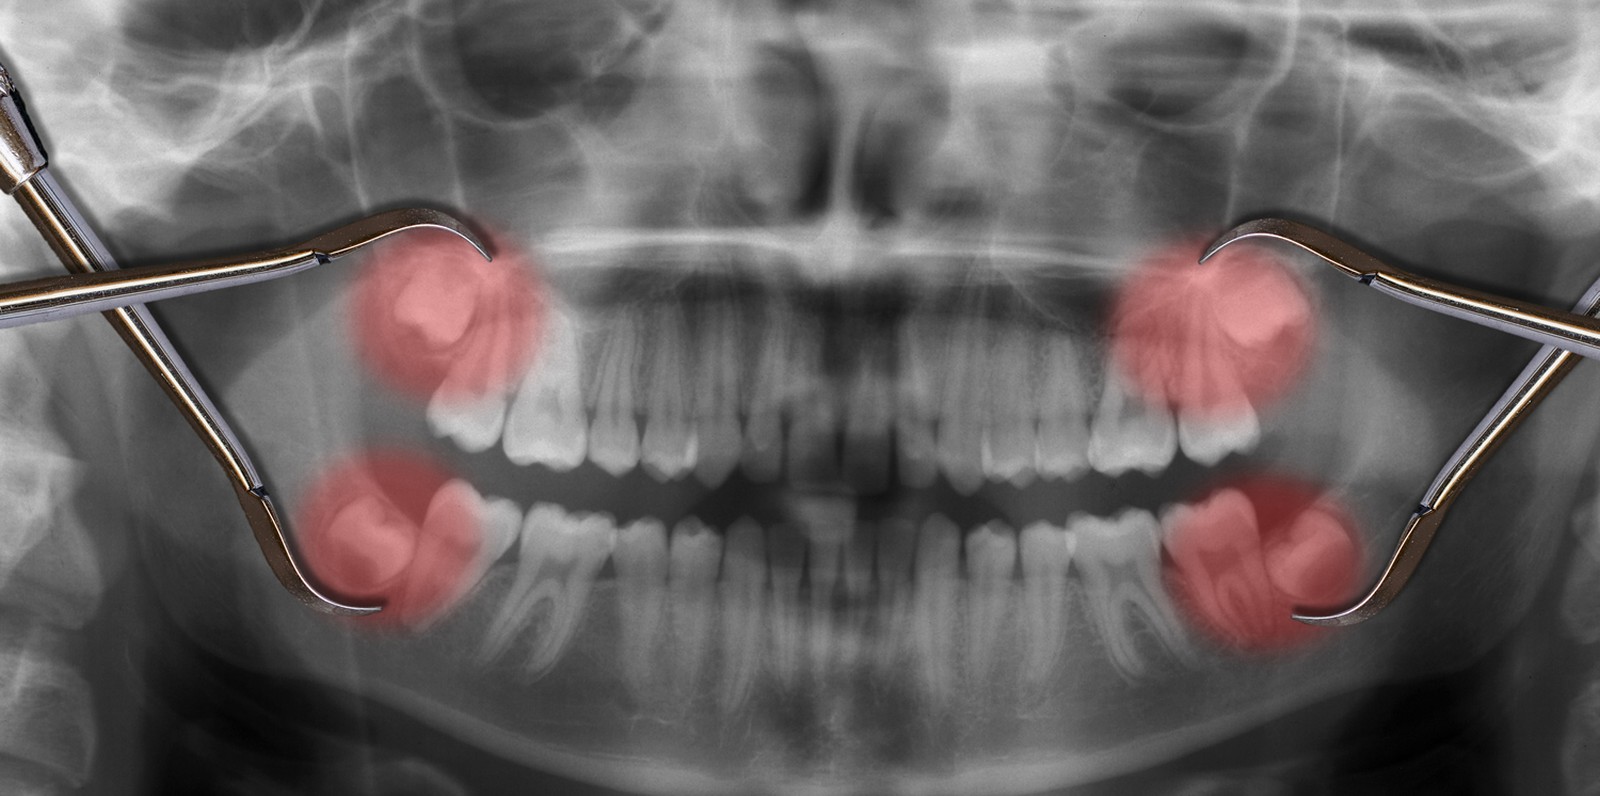

Your dentist will ask you to have an X-ray before having a wisdom tooth removed, so they can see the exact position of the tooth in the gum. This will allow your dentist to work out the best way to perform the extraction of wisdom teeth. Often, wisdom tooth removal is a straightforward procedure that your dentist will be able to do at the dental practice, under local anaesthesia.

Sometimes, your wisdom teeth don’t come through properly, meaning they’re impacted. This can cause problems such as pain, swelling and infection. Having your wisdom teeth taken out can ease these symptoms.

They can get partially stuck in your gums or grow at an angle. This is called an impacted wisdom tooth. Even impacted wisdom teeth don’t always need to be taken out if they aren’t causing any symptoms.

Sometimes though, the way an impacted wisdom tooth is positioned can make it easy for food and bacteria to get trapped around the gum. This can lead to swollen and sore gums (pericoronitis), tooth decay and infection. If you’re having problems such as these, your dentist may recommend taking the impacted tooth out.